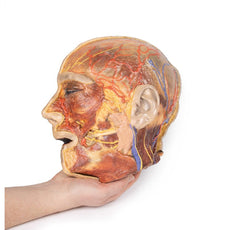

The face: On the right side of the head the parotid gland has been removed to reveal the facial nerve and all its branches (temporal, zygomatic, buccal, marginal mandibular and cervical) and demonstrate the spatial relations of structures embedded in the gland from superficial to deep (facial nerve, retromandibular vein, external carotid artery). In the surrounding region the temporalis, masseter and posterior belly of digastric are exposed, as are and the facial artery, transverse facial artery and superficial temporal artery. The facial vein and transverse facial vein are clearly visible uniting to form the common facial vein which is joined by the retromandibular vein to form the external jugular vein.

Viewed from the anterior aspect the face has been dissected to display some of the facial muscles around the mouth (buccinator [on the left], orbicularis oris and zygomaticus major). On the left side of the infratemporal fossa has been open to expose the medial and lateral pterygoids.

The lateral pterygoid is divided to show the mandibular division of the trigeminal nerve dividing into the lingual nerve and the inferior alveolar branch. Also on the left side the branches of the ophthalmic division of the trigeminal that supply the skin above the eyebrows and scalp (supraorbital [left only] and supratrochlear nerves [both sides]) are dissected. The submandibular gland is clearly visible below the mandible on both sides as are the facial arteries and veins as they course over the mandible.

This 3D print specimen preserves a series of features of the head and visceral column of the neck:The face: On the right side of the head the parotid gland has been removed to reveal the facial nerve and all its branches (temporal, zygomatic, buccal, marginal mandibular and cervical) and demonstrate the spatial relations of structures embedded in the gland from superficial to deep (facial nerve, retromandibular vein, external carotid artery). In the surrounding region the temporalis, masseter and posterior belly of digastric are exposed, as are and the facial artery, transverse facial artery and superficial temporal artery. The facial vein and transverse facial vein are clearly visible uniting to form the common facial vein which is joined by the retromandibular vein to form the external jugular vein.

Viewed from the anterior aspect the face has been dissected to display some of the facial muscles around the mouth (buccinator [on the left], orbicularis oris and zygomaticus major). On the left side of the infratemporal fossa has been open to expose the medial and lateral pterygoids.

The lateral pterygoid is divided to show the mandibular division of the trigeminal nerve dividing into the lingual nerve and the inferior alveolar branch. Also on the left side the branches of the ophthalmic division of the trigeminal that supply the skin above the eyebrows and scalp (supraorbital [left only] and supratrochlear nerves [both sides]) are dissected. The submandibular gland is clearly visible below the mandible on both sides as are the facial arteries and veins as they course over the mandible.